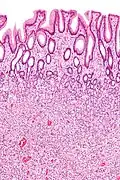

Hyperplastic polyp of the stomach Stomach Elongated, tortuous, and cystic foveolae separated by edematous and inflamed stroma.[14]